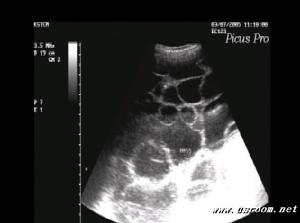

(3)婦科普查發現卵巢腫塊。